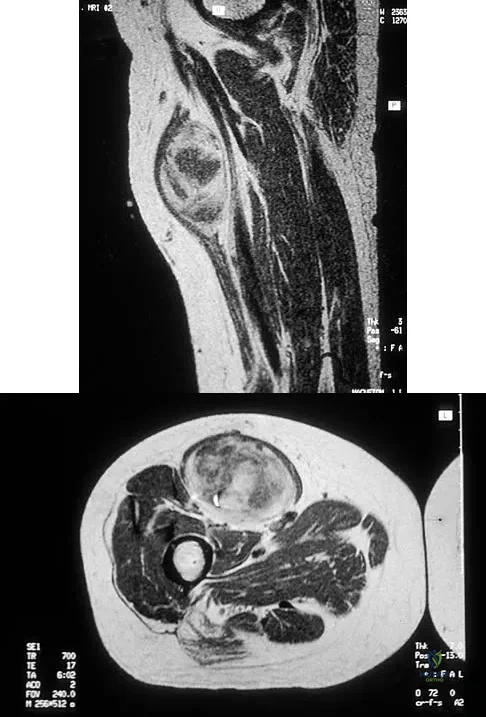

Figures 30a and 30b show the MRI scans of a 51-year-old woman who has had an enlarging soft-tissue mass in her right thigh for the past 18 months. Examination reveals no inguinal adenopathy. Results of a biopsy show a high-grade sarcoma. A bone scan is unremarkable, and a CT scan of the chest shows no evidence of pulmonary metastasis. According to the Musculoskeletal Tumor Society (MSTS) staging system, the tumor should be classified as what stage?

Explanation